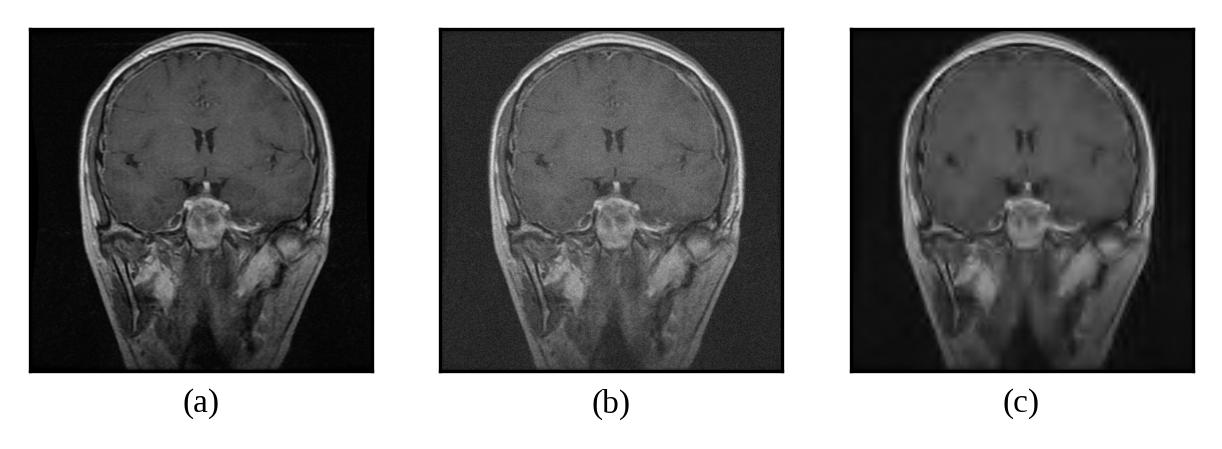

Representative denoising results are illustrated in Figures 2 through 7, demonstrating the visual improvement achieved by both thresholding methods across different noise levels.

Figure 5: (a) Original Image, (b) Noisy Image(μ=0\mu=0, σ=15\sigma=15), (c) Denoised Image (with threshold value τuniversal\tau_{universal})

Refer to caption